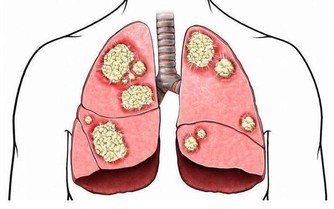

禁慾對前列腺健康不利

前列腺是男性的“生命腺”,對於男性健康十分重要。而前列腺炎卻是男性的高發疾病,有資料顯示約有50%的男性,在一生中的某個時期會受到前列腺炎的困擾。健康男性的前列腺每天分泌約2毫升的前列腺液,主要隨男性排精時排出。如果男性禁慾,讓前列腺液無法正常排出,容易形成前列腺液淤積,進而刺激尿道和前列腺,產生尿頻、尿急、小腹疼痛等症狀,誘發前列腺炎。對於部分慢性前列腺炎的病人,前列腺液中會含有膿細胞白細胞,甚至一些致病菌或微生物。如果不及時排出去的話,它又成了新的病因,前列腺炎反而不容易恢復。因此臨床治療前列腺炎期間,我們常常告誡病人“不要憋精”,要規律過性生活或排精。